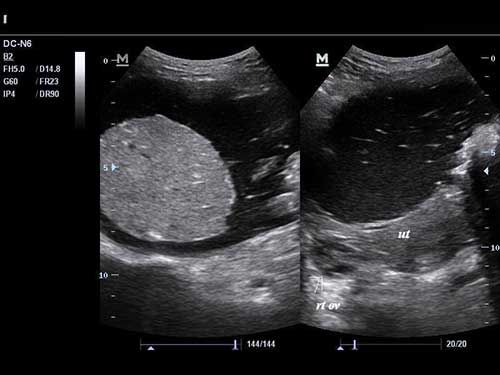

Challenge your diagnostic skills with these images of a pelvic mass.